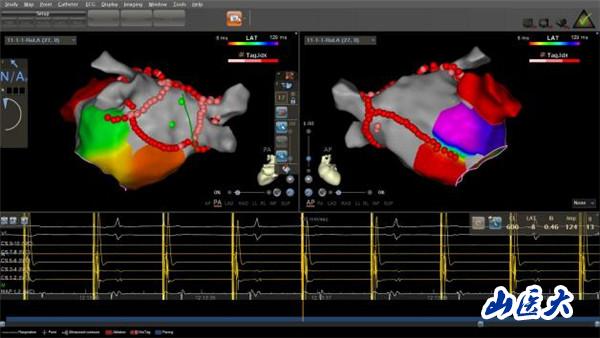

“射频消融术?就是那种有辐射的手术吗?”家属闻此顾虑重重,怕射线给老人的身体带来更大伤害。王睿主任医师解释说,在传统射频消融术中,X射线是实现手术可视化的必要条件,如果不借助X射线进行操作,之前射频消融术是无法实施的。随着医学技术的发展,目前采用CARTO(三维电解剖标测系统)开展零X射线下射频消融术,就像给医生安了一双“慧眼”,无须在X射线透视下,即可实现精准导航。这种新技术,在手术过程中放置标测电极和操作消融大头电极等均采用三维电生理标测系统指导,完全不用X射线透视,却对手术医生技术的熟练程度、导管的操作技术以及心脏解剖三维理解要求极高。通过该技术既能获得准确靶点,缩短手术时间,提升手术安全性,让患者避免了X线辐射,也让医生避免了披“甲”上阵、负重手术,因此被称为绿色电生理射频消融术。

经过充分沟通,由王睿主任医师率领的心电生理团队在CART0指引下,十分精准地操控导管在患者心脏内走行、检查、建立模型、精准定位、消融靶点。术中,老人生命体征平稳,无明显不适。三个小时后,手术顺利完成,老人心脏恢复窦性心律,长期困扰其的房颤终于“驱魔”成功。